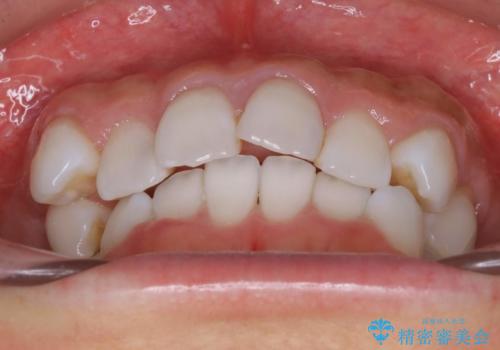

抜歯せずに八重歯のマウスピース矯正

八重歯がシビアな場合、抜歯をしないと治せないケースもありますが、奥歯の位置関係を修正したり、歯のサイズダウンを行うことで、抜歯をせずに改善できる場合もたくさんあります。